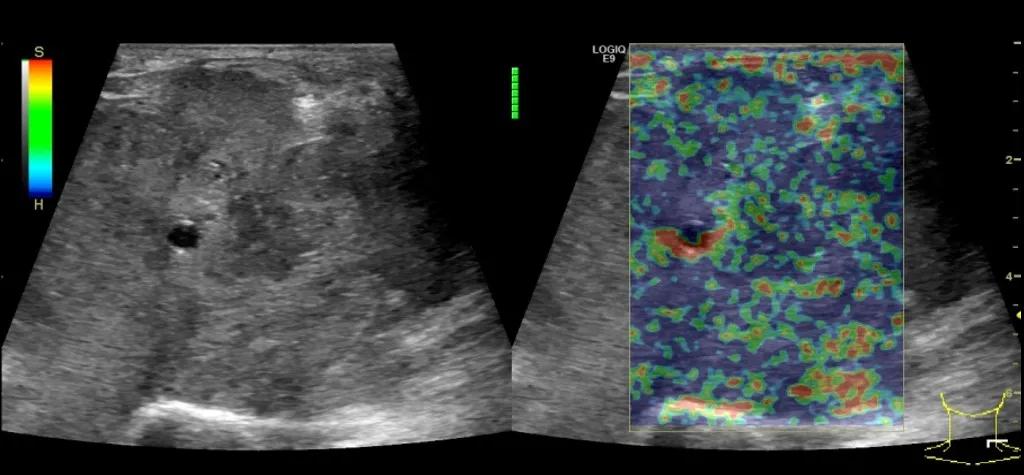

随后,徐栋教授进一步分享了五个临床实战病例,带来了更直观的热消融治疗经验。第一个病例是62岁肺癌患者,术后1年余发现双侧锁骨上淋巴结复发,侵犯神经,存在静脉回流、淋巴回流障碍,肿胀、疼痛非常明显。影像显示患者淋巴结边界不清、形态不规则,存在浸润,血流强化增强。由于患者在系统治疗后进展,且主要目的缓解症状、减瘤。局麻下行热消融术,从后向前逐层消融,热消融之后超声造影即刻评估显示完全充盈缺损,完全覆盖病灶。

(病例1图例)